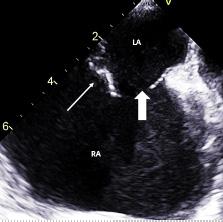

pregnancythreemonthspriorpresentedtotheEDwith suddenonsetofabdominalpainthatwokeherfromsleep. Shereportedthepainassevereanddiffuse,notablyworsein theupperabdomen,withassociatednauseaandlowerback pain.Additionally,thepatientreportedwhitevaginal discharge.Shedeniedanyfever,chills,vomiting,chestpain, shortnessofbreath,diarrhea,orconstipation.

Onphysicalexamination,thepatienthadanoral temperatureof99° Fahrenheit(37.2° Celsius),tachycardiaof 108beatsperminute,bloodpressureof106/71millimetersof mercury,97%oxygensaturationonroomair,andadiffusely tenderabdomenwithvoluntaryguardingandrebound tendernesssuggestiveofperitonitis.APOCUSwas performedtoassessforintraperitonealfree fluid.Itrevealeda complexcollectionof fluidwithinternalechoesinthe hepatorenalspaceraisingconcernforaloculatedinfection (See Image and Video).

Bowelgasobscuredthetransabdominalsuprapubic imagesofthepelvicorgans.Intravenous(IV)morphinewas administeredforpaincontrol.Pelvicexaminationrevealed cervicalmotiontendernessandwhitedischargecomingfrom theexternalcervicalos.Laboratoryanalysiswasremarkable forawhitebloodcellcountof18.9 × 103 permicroliter (K/μL)(referencerange4.5–11.0K/μL)withaneutrophil predominanceof93%.Electrolytes,lipase,hepaticfunction panel,andlactatewerewithinnormallimits.Serum β-human chorionicgonadotropinwasnegative,andtherewas anunremarkableurinalysis.Broadspectrumantibiotics wereinitiated.

Transvaginalultrasoundperformedbyradiologyreported asymmetricenlargementoftherightovarywithacomplex,

4.2-centimeter(cm)cyst.Therewasasymmetricincreased flowtotherightovaryonDopplerevaluation.Gynecologic consultationwasobtained,andduetoconcernforright ovariantorsion/detorsionthepatientwastakenfor diagnosticlaparoscopy.Thepatientwasfoundtohavea rupturedTOAwith200milliliters(mL)ofpurulent fluidin theperitonealspace.Aperitonealwashoutandcystectomy wereperformed,andthepatientwasadmittedforIV ceftriaxone,doxycycline,andmetronidazole.Shewas dischargedonpostoperativedaythreewitha14-day courseoforaldoxycyclineandmetronidazole.The intraperitoneal fluidsamplecollectedduringlaparoscopy grewGAS.

Abdomino-pelvicPOCUSmayguidetriage,diagnosis, andmanagement,assistingtheclinicianininvestigatinga rangeofdiseaseentitiesincludingbiliarypathology, abdominalaorticaneurysm,orTOA.3–5 Bedsideultrasound isgenerallyreadilyavailableintheEDsettingandmayserve asanadditionalmodalitytoidentifyunusual findingsearlyin thepatient’sclinicalcourse.Itdoesnotrequireionizing radiationandisnottimeintensivetoperform.Cliniciansmay considerearlyuseofPOCUSforperitoneal findings,as evidencedinthiscasepresentation.Inconjunctionwith informationobtainedonhistoryandphysicalexamination, theunusual,rightupperquadrantPOCUS findingsof intraperitoneal fluidwithloculationscausedconcernfora disseminatedpelvicinfection.Thiswasconfirmedasa rupturedTOAwithamoderateamountofpurulent, intraperitonealfree fluidontheoperativereport.Fitz-HughCurtissyndromewasaconcerngiventhecomplicated fluidvisualizedwithPOCUS,buttherewasnocommentof violin-stringadhesions,adhesions,or fibrousadhesions betweentheanteriorhepaticcapsuleandparietal peritoneumnotedonthelaparoscopicoperativereport, althoughitisunknownwhetherthisanatomicarea wasevaluated.

Intraperitoneal fluidiseasilyvisualizedonultrasound, andwhencomplex fluidwithloculationsisencountered,the differentialdiagnosisincludesmalignancy,inflammation, andinfectiousprocesses.6 Similar findingsofseptated intraperitoneal fluidhavebeendocumentedincases of Ctrachomatis inPID,7 cholecystitis,8 and tubercularperitonitis.9

GroupAstreptococcusisararecauseofpelvic in fl ammatorydisease,usuallyseenintheperipartum period,inpatientswithanIUDorwhohavehadother recent,invasivegynecologicprocedures.Inapatientnot respondingtoantibioticsadministeredfortypicalPID coverage,GASshouldbeconsideredasapossibleetiology andapenicillin-basedantibioticadministeredtoprevent progressiontotubo-ovarianabscessformation,peritonitis, andsepsis,particularlyincasesofreturningpatients previouslytreatedwithantibiotics.Bedsideultrasound shouldbeperformedinpatientspresentingwithabdominal pain,anduncommon fi ndingsshouldtriggerfurther investigation.Toourknowledge,noothercasesofloculated fl uidinthehepatorenalspaceassociatedwithPIDhave beenreported.

Video. Rightupperquadrantultrasonographyusingcurvilinear probefanningthroughthecoronalplanedemonstratingascitesand septationsinapatientultimatelydiagnosedwithpelvic inflammatorydisease.